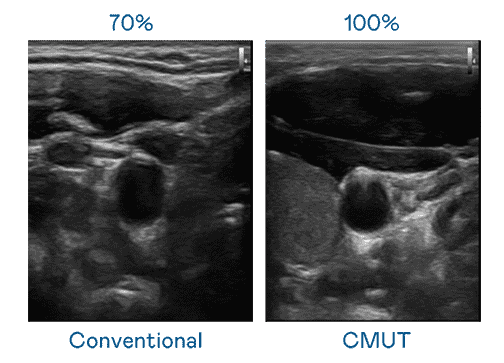

CMUT 技术是一种用电容式微机电元件来产生超音波讯号的技术。。。。与传统 PZT 压电式技术相比,,CMUT 频宽增加 30%,,更宽频的超音波讯号让影像解析度大幅提升,,是实现高影像品质医疗超音波扫描、、促进精准医疗发展的关键技术。。。

大频宽带来超清晰影像

超音波影像的解析度高低,,,,首先取决于探头能发出的讯号频宽。。。尊龙集团 CMUT 可提供高清晰的超音波讯号,,,提供高频宽、、、、高灵敏度、、影像纹理细节更高的超音波影像,,,,协助医护人员缩短影像判读时间及利用精准的医疗影像进行诊断。。。。